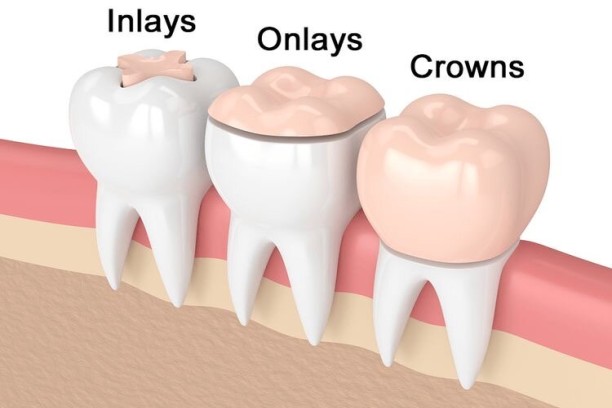

Inlays & Onlays

Custom-made restorations for repairing moderately damaged teeth with precision.